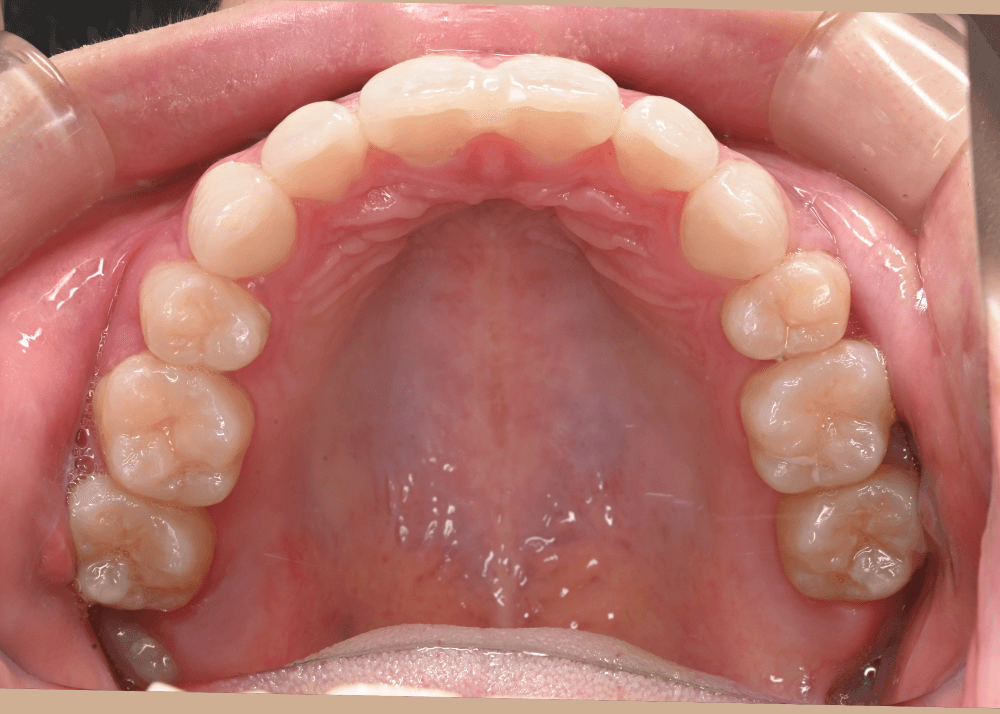

まとめ・治療後の変化

治療後は、気にされていた「口ゴボ(口元の突出感)」が改善され、自然でバランスの良い口元になりました。

隙間のあった前歯も、しっかり噛み合うようになっています。

治療後(32か月)

上顎前突(口ゴボ)を解消。唇がEラインの内側に入り、自然な口元に改善し、噛み合わせも整いました。 ※治療結果は患者様によって個人差があります。 |